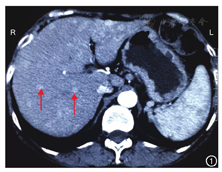

患者女,49岁,因体质量下降2年,双下肢及面部皮疹7个月,于2012年10月收入我院。患者本次入院前就诊经过:(1)于2010年10月开始出现口干、体质量下降,外院检查提示血糖、尿糖增高,诊断为2型糖尿病,给予降糖治疗,血糖控制不佳,体质量进行性下降。(2)于2011年2月15日行腹部CT检查示肝脏多发占位性病变(图1)。(3)于2011年3月2日行PET/CT检查示肝脏内弥漫性分布的结节状略低密度病变,肝左叶病变融合成片,肝脏炎性病变可能,建议行穿刺活组织检查;脾脏肿大,脑、肺、胰腺、胆囊显影未见异常(图2)。实验室检查:HBV、HCV相关指标均为阴性,血清肿瘤标志物AFP、CA19-9、CA125、CEA、CA242等均正常。影像学检查未见其他部位明显占位性病变。肿瘤标志物检查不支持恶性肿瘤诊断,患者拒绝行穿刺活组织检查。(4)2012年4月,患者出现双下肢、面部皮疹,呈进行性加重,在外院皮肤科按湿疹给予对症治疗,效果不佳。